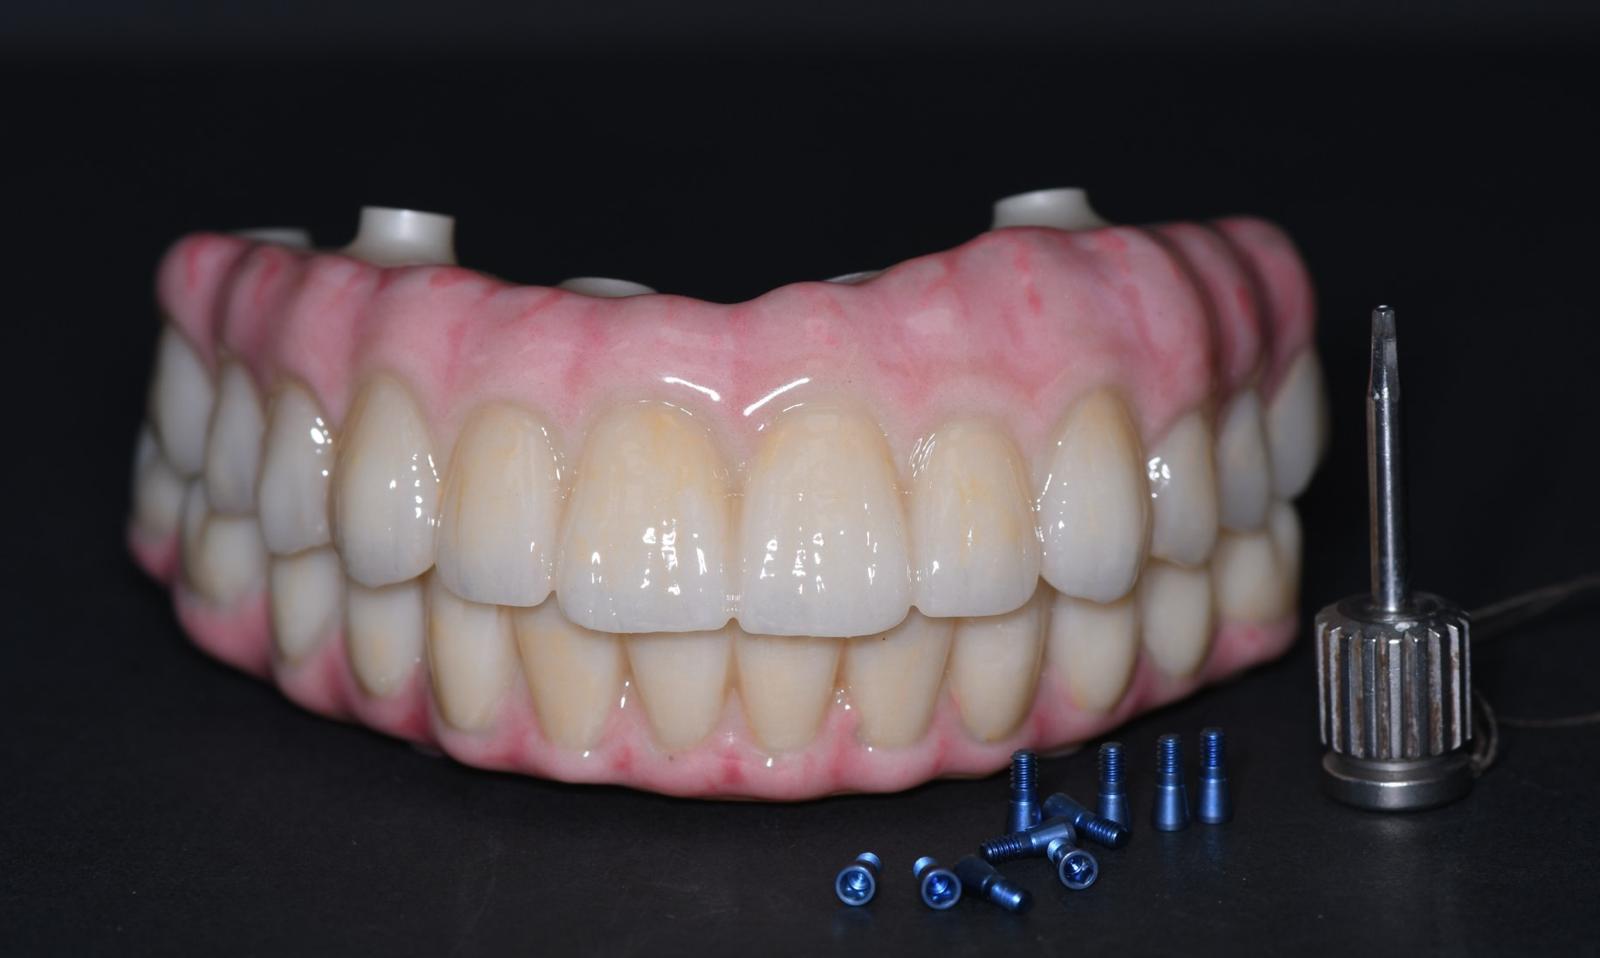

The revolutionary All-on-X (AOX) model-less workflow has become a reality through seamless integration of state-of-the-art technologies: interactive implant planning software, guided surgery systems, intraoral scanning (IOS), advanced 3D printing, and photogrammetry. Our innovative CAD-CAM protocols dramatically streamline the treatment process, reducing appointment frequency, chair time, and prosthetic delivery intervals. We've pioneered multiple digital workflows that ensure precise implant position recording and bite capture for full-arch implant rehabilitation.

The latest breakthroughs in 3D printing technology and materials enable same-day provisional restoration with unprecedented predictability. Clinicians can now consistently produce highly accurate temporaries that achieve perfect fit on multi-unit abutments (MUAs), whether using freehand or guided surgical approaches.

- Learn advanced techniques for direct MUA restoration using Rosen, Powerball, Vortex, or DESS Flat Seat Screws, eliminating the need for Ti-bases or Ti-copings